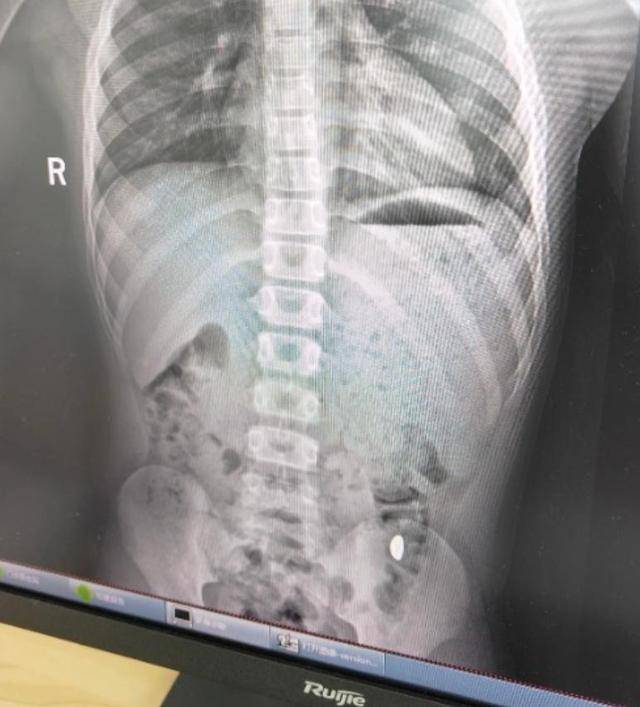

昆山市第五人民医院门诊病历单显示,患儿5天前误吞约10克黄金,其间解两次大便未发现,目前无腹痛、呕吐等症状,诊断结果显示胃内有异物。